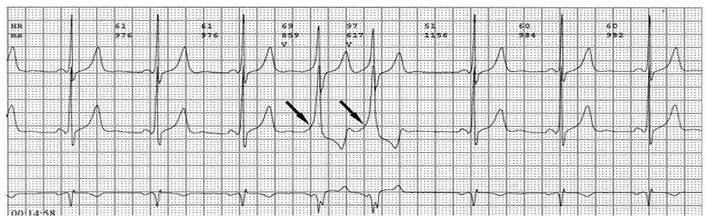

各旁路引起预激的心电图特征如下:

1、房室旁道

(1)PR间期(实质上是P-δ间期)缩短至0.12秒以下,大多为0.10秒;

(2)QRS时限延长达0.11秒以上;

(3)QRS波群起始部粗钝,与其余部分形成顿挫,即所谓预激;

(4)继发性ST-T波改变。

上述心电图改变尚有分为A、B两型的。A型的预激波和QRS波群在V1导联均向上,而B型V1导联的预激波和QRS波群的主波则均向下;前者提示左室或右室后底部心肌预激,而后者提示右室前侧壁心肌预肌。这种分类方法虽然受到预激是不同部位旁路所致的多变QRS波群的限制,但有助于区别旁路的心室端在左或右、前或后,因而沿用至今。

2、房结、房希旁道

PR间期少于0.12秒,大多在0.10秒;QRS波群正常,无预激波。这种心电图表现又称为短PR、正常QRS综合征或L、G、L(Lown-Ganong-Levine)综合征。

3、结室、束室连接

PR间期正常,QRS波群增宽,有预激波。预激综合征室上性心动过速发作时,预激表现大多消失,心电图表现为QRS波群形态正常的室上性心动过速。并发房扑或房颤时,QRS保持预激特征的不少见,心电图表现为QRS波群畸形宽大的房扑或房颤;心室率大多超过200次/分,甚至可达300次/分。房扑时可呈1:1房室传导,并可能辨认房扑波。房颤时心室律不规则,长间歇之后可见到个别QRS波群形态正常(可能为旁路不应期延长,房室结内隐匿传导作用消失后,冲动全部或大部经房室结传导所致),并可能辨认房颤波。心室率极快时,还可伴有频率依赖性心室内传导改变。

1、典型预激综合征

(1)P-R间期<0.12秒,P波正常;

(2)QRS时间>0.11秒;

(3)QRS波群起始部分变粗钝,称为预激波δ波

(4)继发性ST-TT改变。临床上又分为两型:A型预激:预激波和QRS波群在V1导联向上,其旁道位于左侧房室瓣环周围。B型预激:预激波和QRS波群的主波V1导联向下,在左胸导联V5向上,其旁道位于右侧房室瓣环的周围。